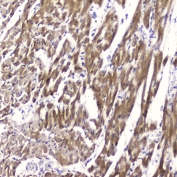

IHC testing of FFPE human esophageal squamous cell carcinoma with FABP3 antibody at 2ug/ml. HIER: boil tissue sections in pH6, 10mM citrate buffer, for 10-20 min followed by cooling at RT for 20 min.